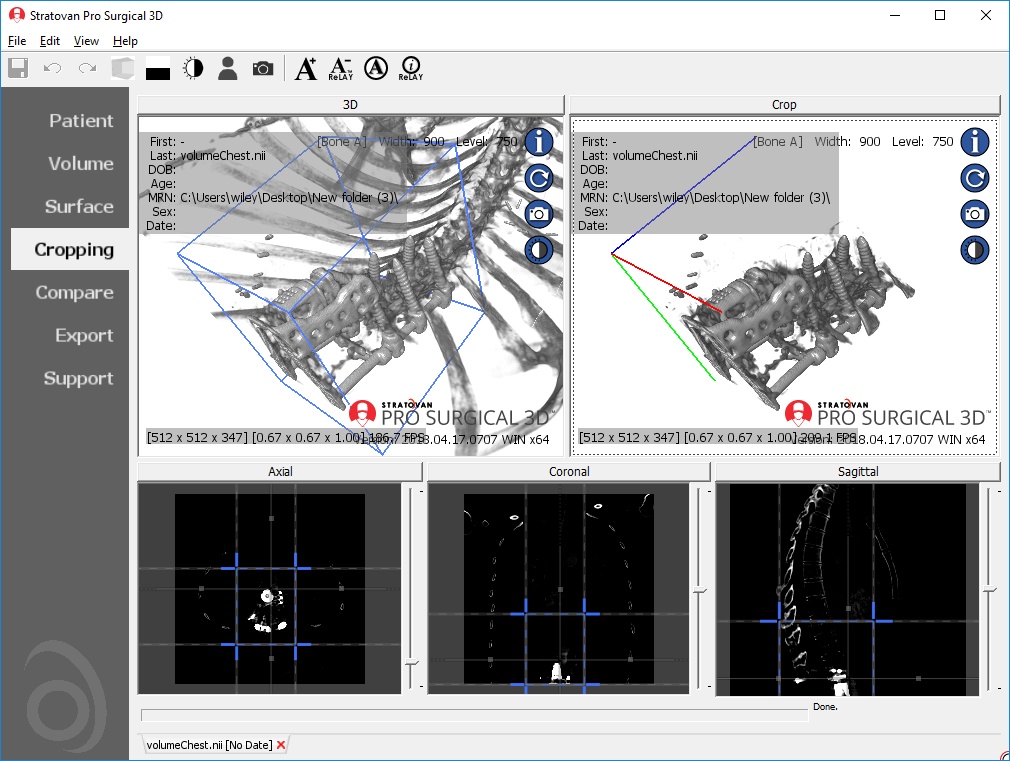

Performs 3D reconstruction and volume rendering.

Multi-planar slicing.

Axis-aligned cropping with context.